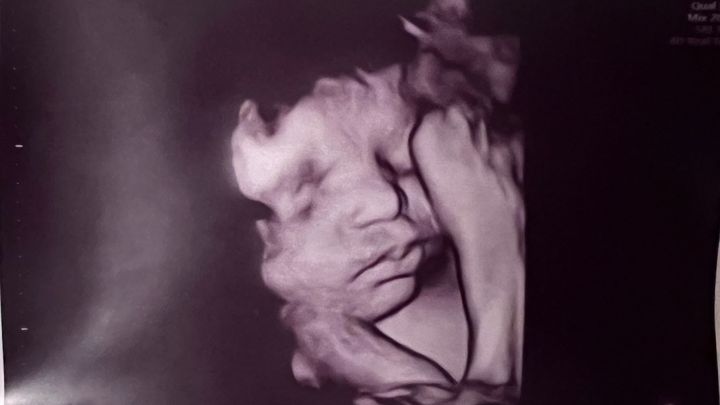

My name is Sam and I work with Jacey. Jacey and Mickey are welcoming a baby in September and as exciting as that can be, they were met with some hard news that their baby boy was diagnosed with HLHS, hypoplastic left heart syndrome. This requires 3 open heart surgeries, 2 of which will likely be before he is 6 months old. They will be temporarily relocating to Shands in Gainesville from Tallahassee. They are preparing to be hospital bound for a least a month and a half and will have extra expenses for housing and food on top of the medical bills to come. If we can help support Jacey and Mickey financially feel supported, it will help them concentrate on family and bring their precious home. As any parent can imagine, this is a scary time for Jacey Mickey and Cooper. Let’s gather together to support their family.